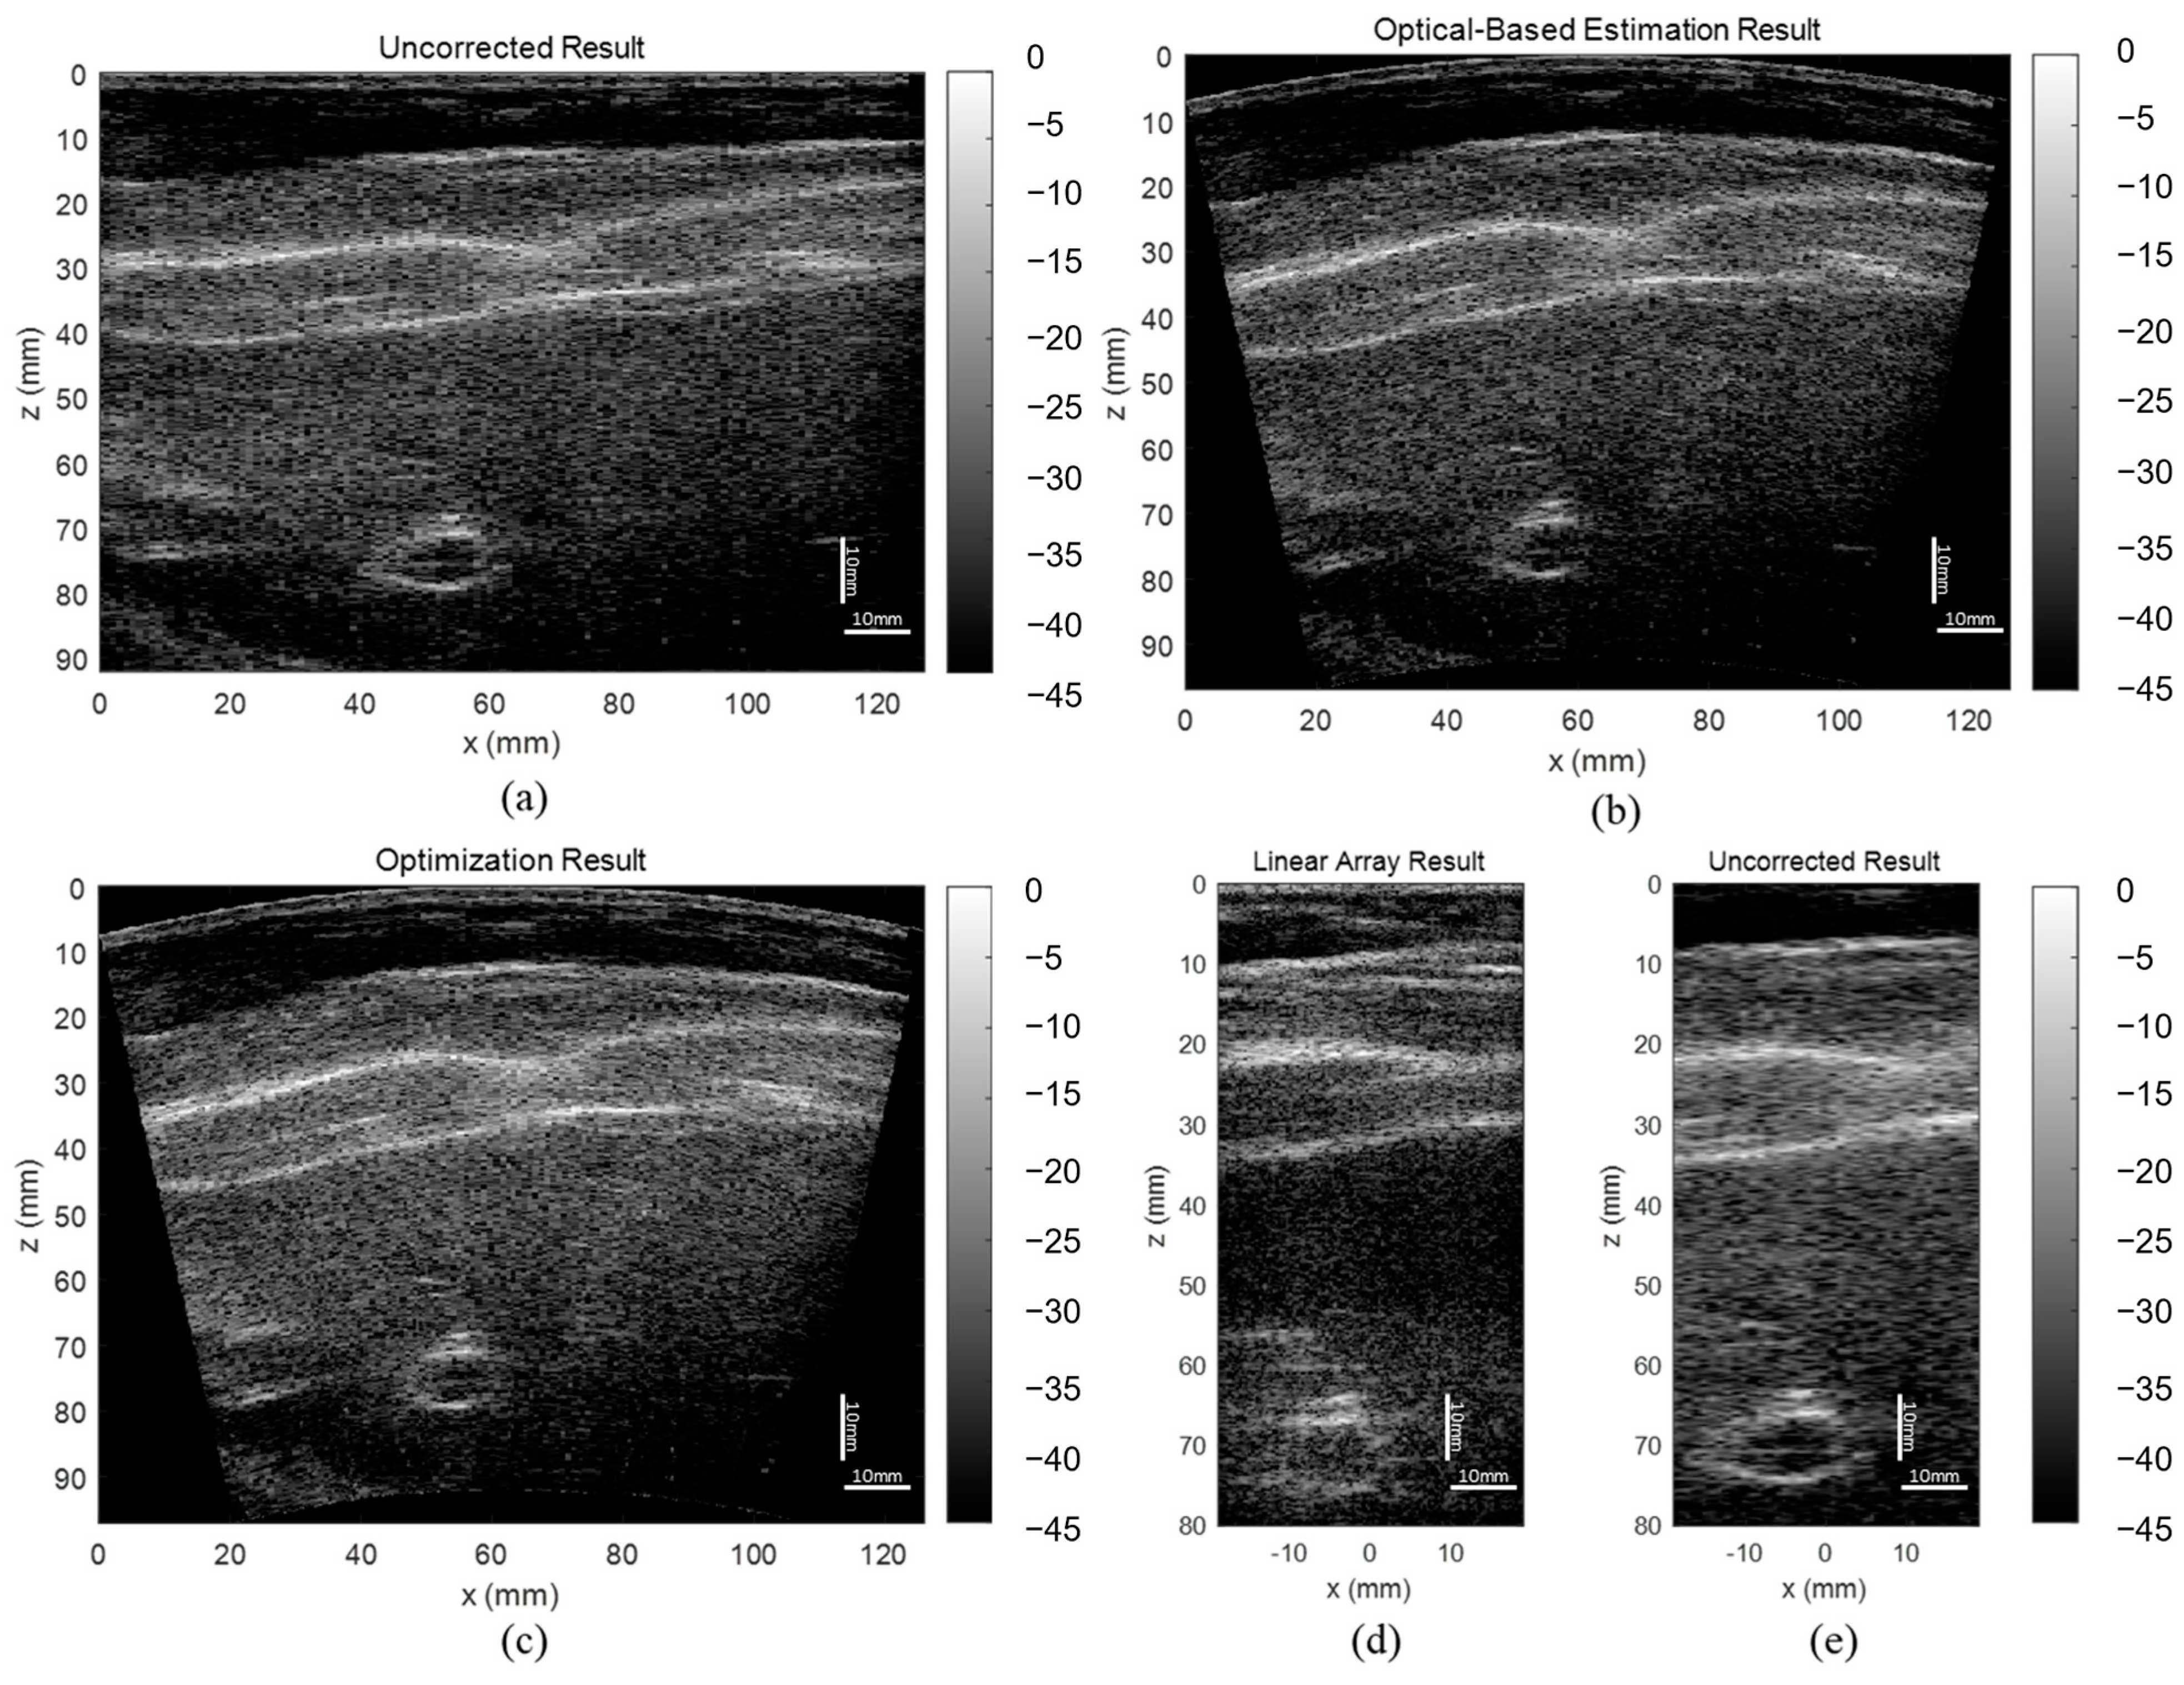

3.3. ABDFAN Phantom and Liver Scan Results

The uncorrected, optical-based estimation, and optimization results of the ABDFAN phantom and liver scan are shown in Figure 10 and Figure 11. The ground truth images from the linear array transducer are shown in Figure 10d and Figure 11d, and the same regions are cropped from the flexible array transducer results, and examples of the uncorrected results are depicted in Figure 10e and Figure 11e. The uncorrected results have significant distortions compared with the ground truth and corrected results. To quantitatively analyze the distortion, the cysts, blood vessels, and mussels are segmented as shown in Figure 12, and the Dice score, Jaccard index, and Hausdorff distance between the results and ground truth are evaluated and listed in Table 5, Table 6, and Table 7. The results show that both estimation and optimization algorithms can correct the distortions of the reconstructed image, and there is no significant difference between the two algorithms. The CNR and GCNR of the center cyst in the ABDFAN phantom and the large blood vessel in the liver scan are listed in Table 5, Table 6, and Table 7. In conclusion, the images reconstructed by both algorithms have an overall higher accuracy and contrast than the uncorrected images, and the optimization algorithm has a slightly better performance on estimating the array shape.

Figure 10.

Reconstructed images of the ABDFAN phantom (a) without array shape correction, (b) with optical-based estimated shape and (c) optimized shape, (d) ground truth image from the linear array transducer, and (e) cropped image with the same region as the ground truth.